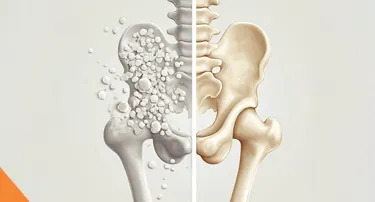

What Is Osteoporosis? Understanding Bone Health and Risk Factors

Osteoporosis is a bone disease. In this, bones lose their density and strength, becoming weak and fragile. It occurs when the body breaks down old bone more quickly than it can make new bone, resulting in porous, less dense bones.

How To Prevent Osteoporosis & Strengthen Your Bones

Osteoporosis is a common but often overlooked disorder that weakens and makes bones brittle, leading to a higher risk of fractures. Osteoporosis predominantly strikes older adults, but it is something that every person, regardless of age, needs to take notice of.